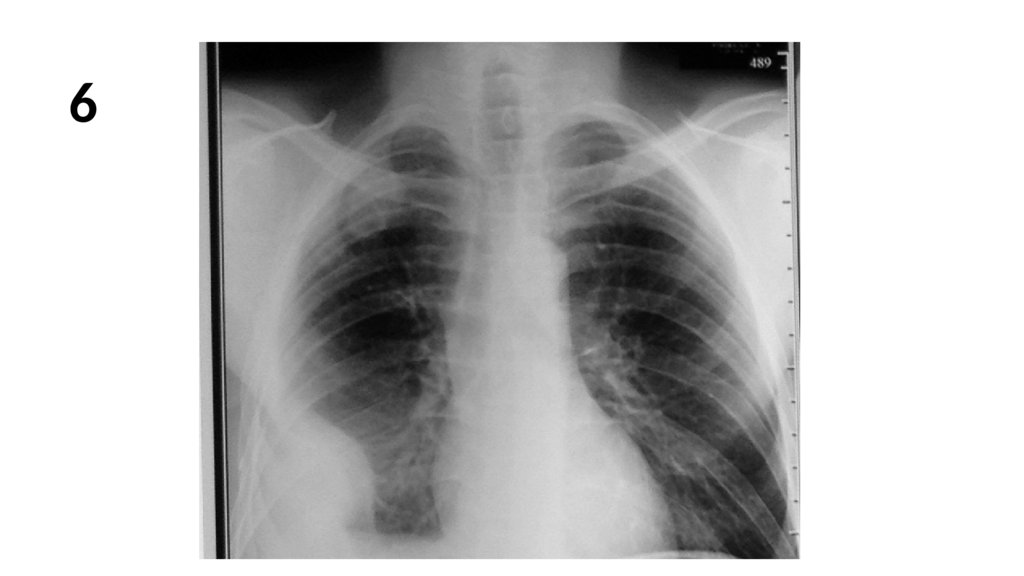

6.

6